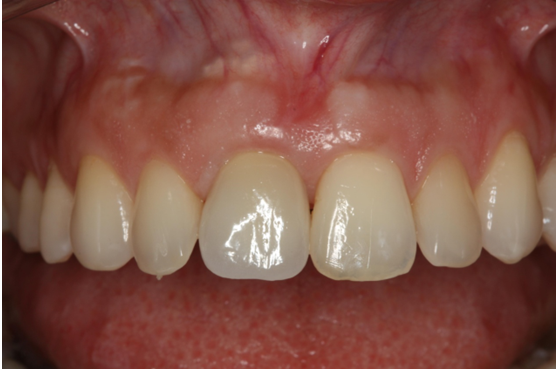

4. Εμφυτεύματα στην αισθητική ζώνη

Τοποθέτηση εμφυτεύματος στην πρόσθια (αισθητική) ζώνη. Ασθενής ετών 30 προσήλθε στο ιατρείο παραπονούμενη για πόνο, οίδημα και πυορροή στον κεντρικό τομέα άνω δεξιά.

Το δόντι είχε κακή πρόγνωση (κάταγμα ρίζας) και για το λόγο αυτό έγινε εξαγωγή και ταυτόχρονα δημιουργία νέου οστού με τοποθέτηση μοσχεύματος και μεμβράνης (οστική ανάπλαση). Μεθύστερα, τοποθετήθηκε εμφύτευμα και η επούλωση κρίθηκε απολύτως επιτυχής.

ΑΡΧΙΚΗ ΚΛΙΝΙΚΗ ΕΙΚΟΝΑ

ΧΑΜΟΓΕΛΟ ΑΣΘΕΝΟΥΣ (ΑΡΧΙΚΗ ΕΙΚΟΝΑ)

ΕΠΟΥΛΩΣΗ ΜΕΤΑ ΤΗΝ ΑΝΑΠΛΑΣΗ

ΤΕΛΙΚΗ ΕΙΚΟΝΑ ΑΣΘΕΝΟΥΣ (3 ΜΗΝΕΣ ΜΕΤΑ)